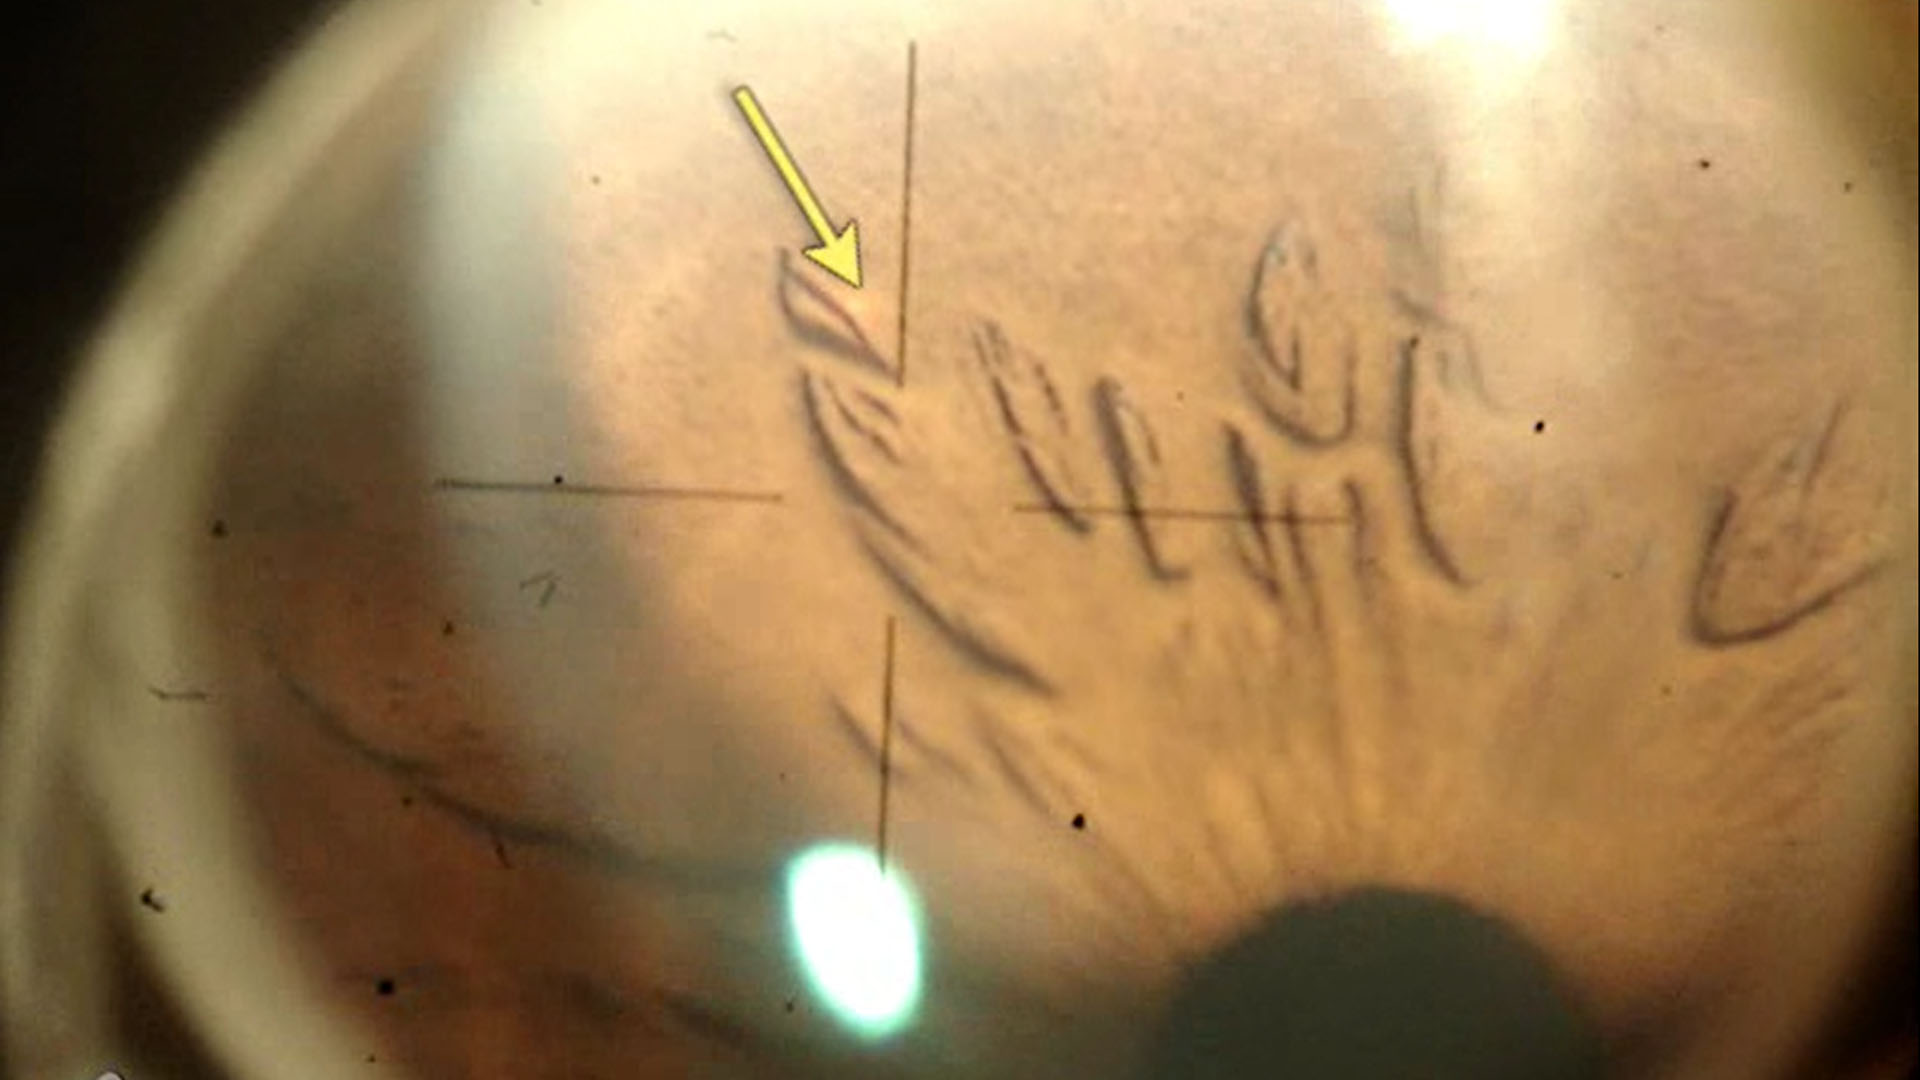

<홍채절개술의 치료부위 및 크기>

대개 홍채의 상반부를 절개하지만, 어느 사분면에 해도 무방합니다.

다만, 홍채절개술은 12시 방향을 피해서 시술해야합니다.

12시 방향에는 레이저로 인해서 생기는 공기방울이 모여서 시술중에 시야가 흐려질수 있기 때문입니다.

대개는 보통은 11시나 1시 방향에 시술을 시행하게되고, 특히 상비측 홍채에 시술하게되면 코쪽망막 주변부로 향하게 하는 장점이 있습니다.

위치상은 홍채의 중간주변부, 중심2/3와 주변 1/3의 경계정도에서 홍채의 얇은 부분(crypt)에 시행하게됩니다.

그러나 해당위치에 각막혼탁이 있거나, 주변부 홍채가 각막과 너무 가까워서 각막 손상이 우려되는 경우에는 더 중심쪽으로 오기도합니다.

적절한 홍채절개술의 크기는 약 500 um (0.5mm 직경) 이며, 최소 200um (0.2mm)는 되어야 합니다.